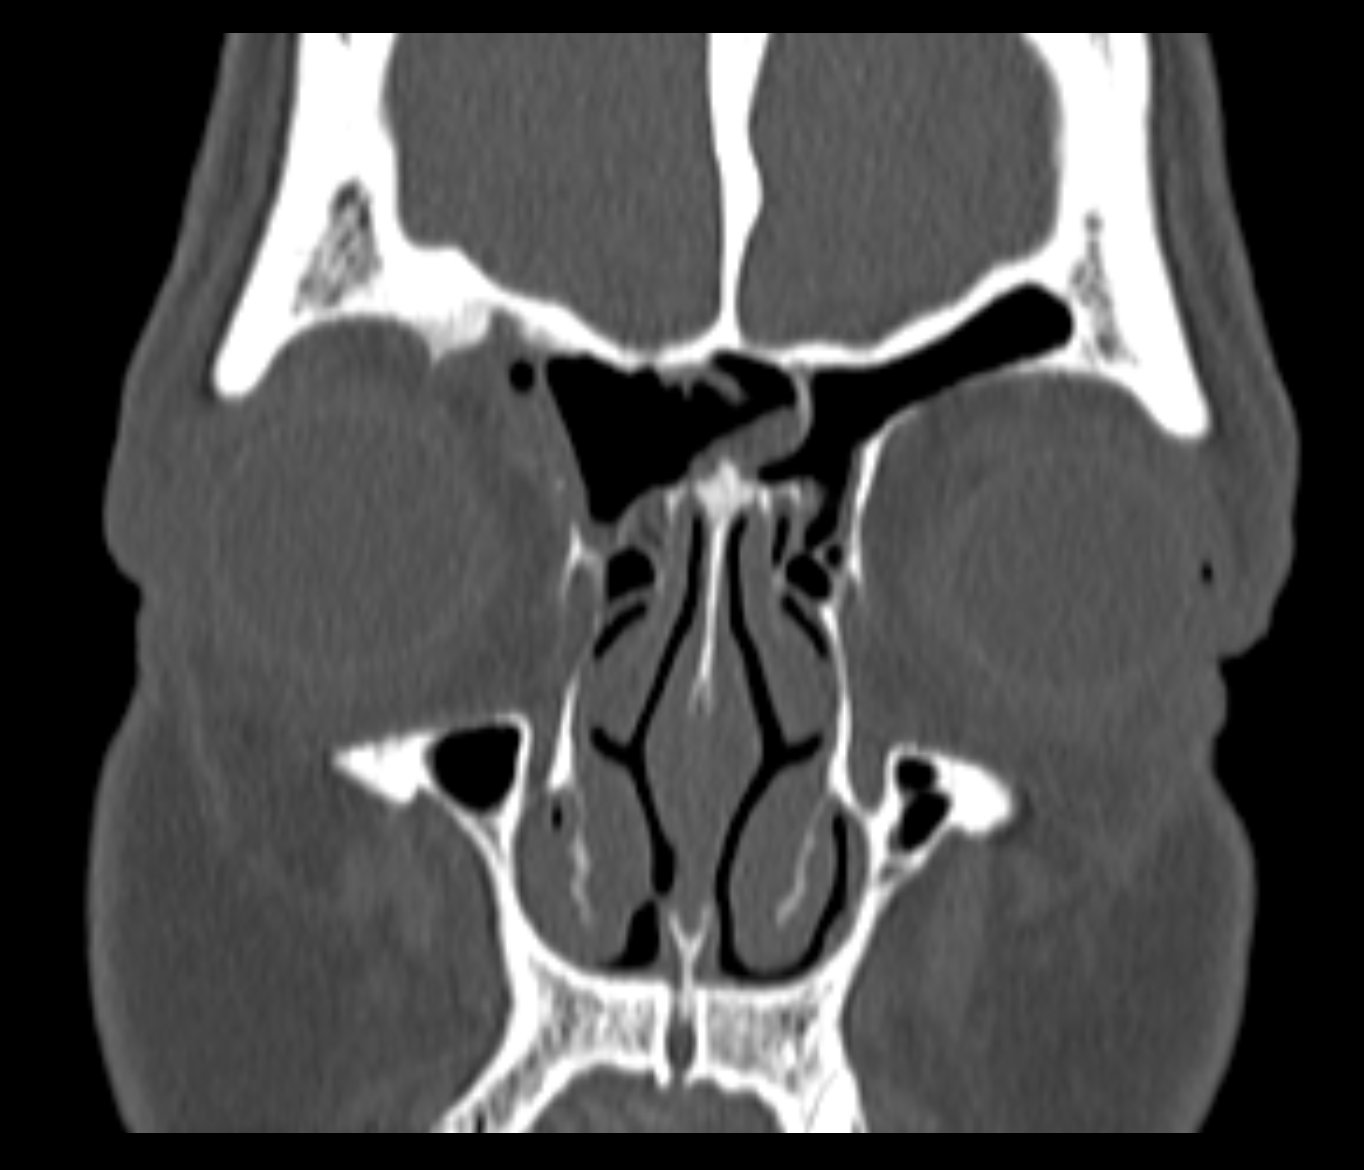

Examenul clinic ORL și examenele imagistice complementare (CT, RMN sinusuri paranazale) pun în evidență o formațiune tumorală osteogenică a sinusului frontal drept, protruzivă în unghiul supero-intern al orbitei, extinsă medial către sinusul frontal stâng.

- Se expune formațiunea tumorală osteomatoasă care ocupă în totalitate cavitatea sinusală frontală dreaptă, se extinde către sinusul frontal controlateral și către orbita dreaptă, creând presiune pe atmosfera celulo-grasoasă periorbitară la nivelul unghiului supero-intern OD. Formațiunea este intens aderentă la nivelul peretelui sinusal postero-superior. Aceasta prezintă două zone de consistență diferită.

Ziua 1 postoperator, pacienta efectuează CT sinusuri paranazale de control care certifică ablația completă a formațiunii.